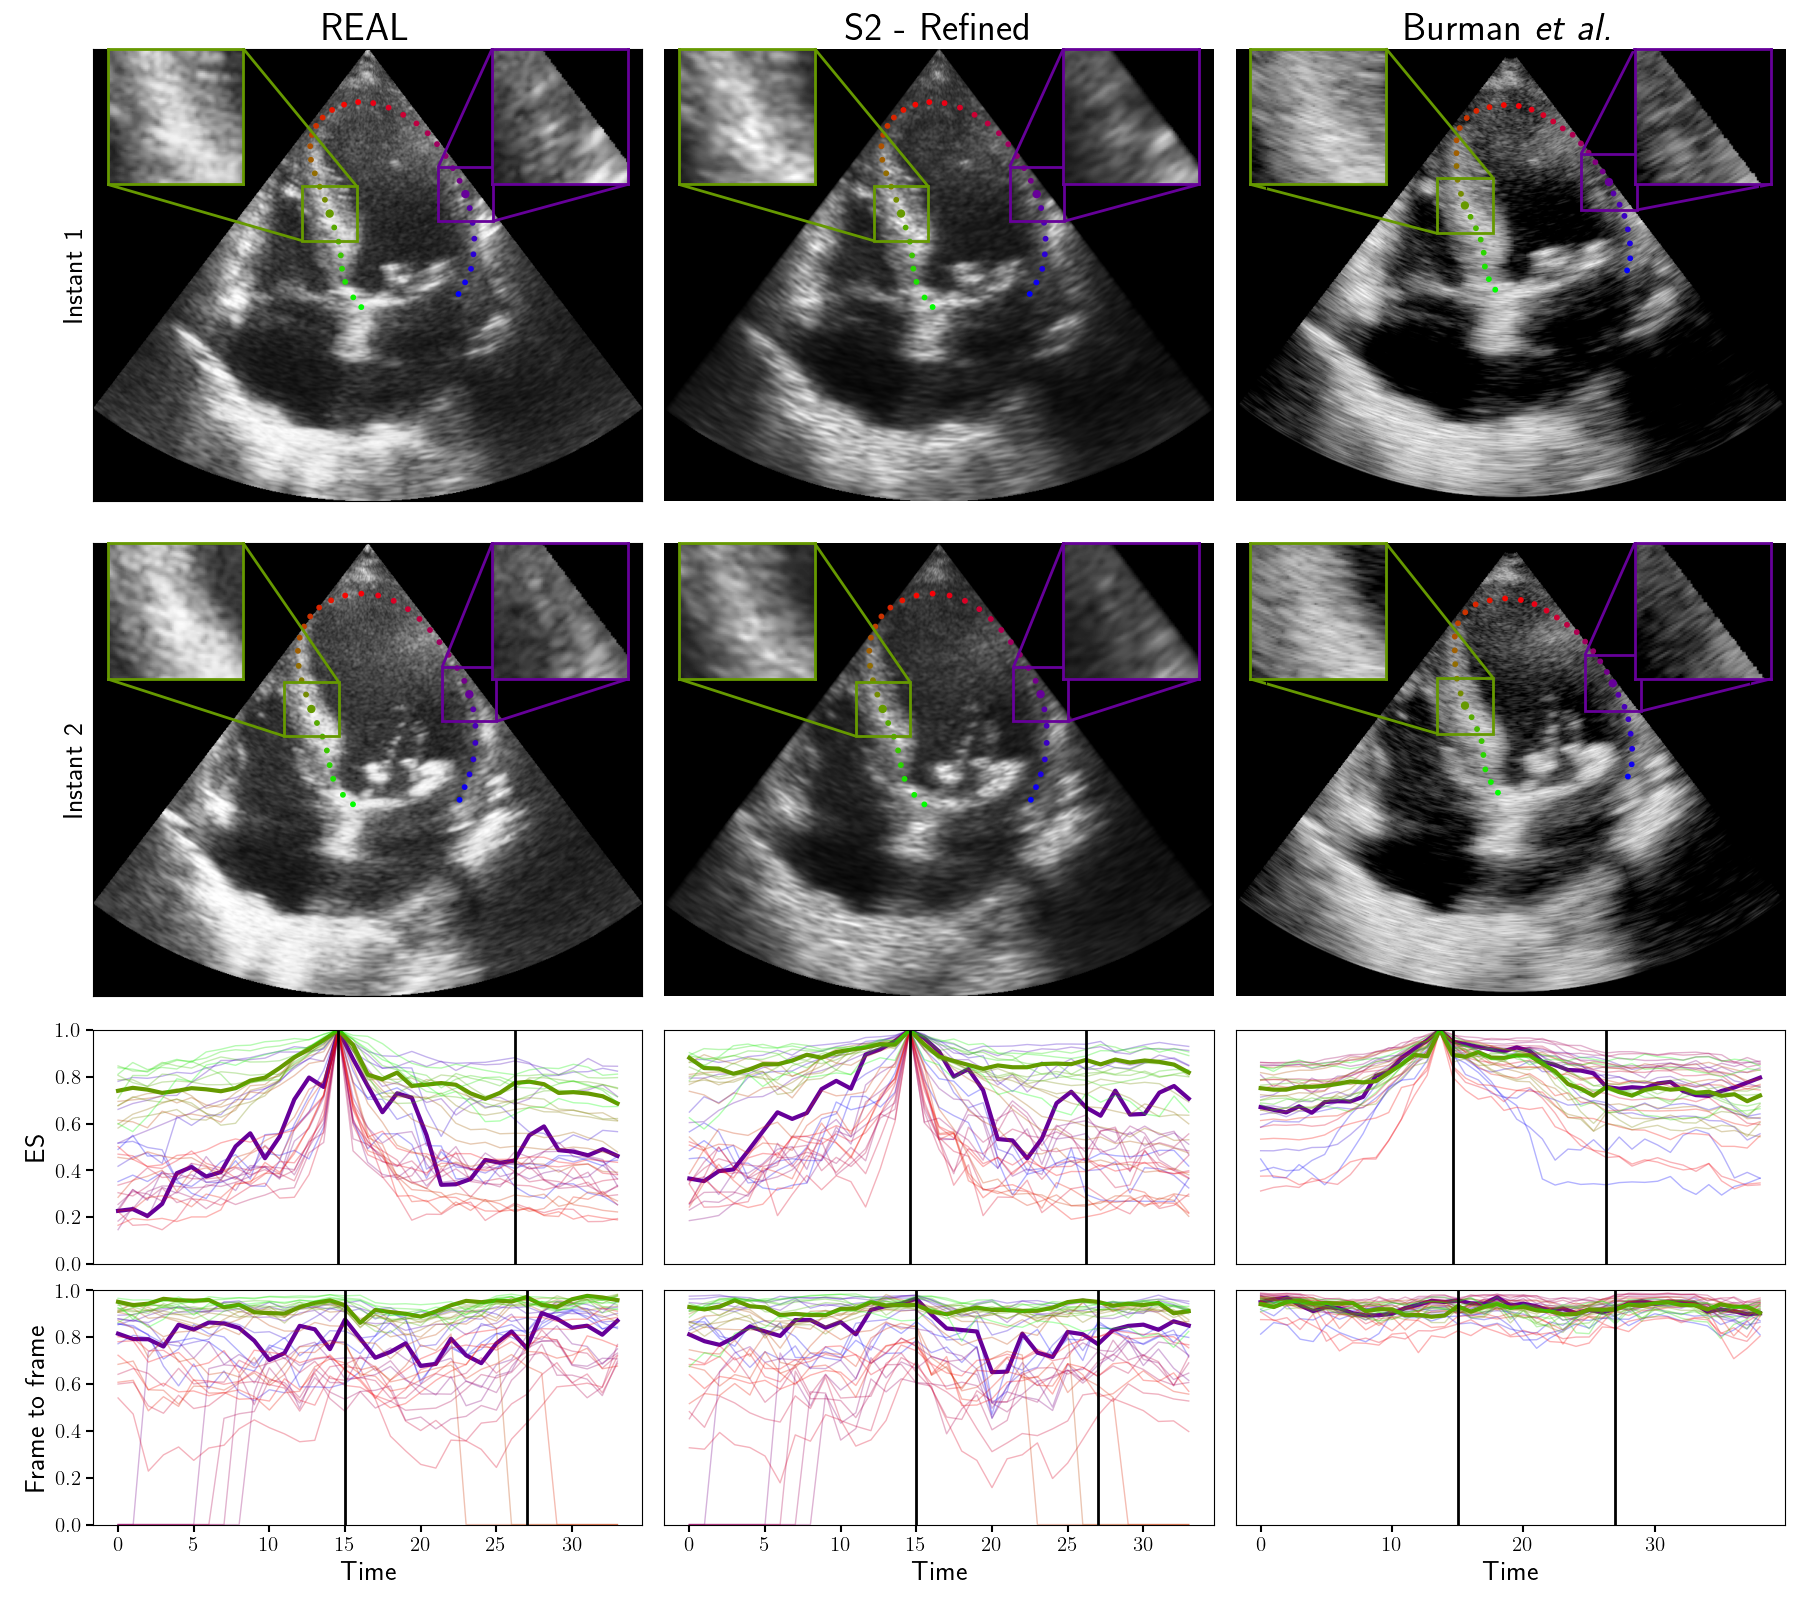

Figure 3: Example of two distinct frames from real and simulated sequences. Correlation curves with ES reference and frame-to-frame reference are shown in the last two rows for the 36 center line points. The highlighted curves represent the points in the zoom regions of the images. Black vertical lines indicate the first and second instants.

Figure 4: Comparison of refined strategy 2 with simulation from [5]. Display similar to Fig. 3.

Results are shown in Table I. The best results are obtained with strategy S2 - Refined, which outperforms S2 and the best version of strategy 1: S1-30. The results show that decreasing the value of pp decreases the MAE and average correlation. However, reaching S1-30, the frame-to-frame MAE increases, and the average correlation level is lower than the real data, indicating the correlation is too low. Qualitative results in Fig. 3 confirm the S1-30 simulation has too little correlation. It also shows that both S1-90 and S1-30 have very constant correlation throughout the video, but at different levels. On the other hand, both versions of strategy 2 have lower correlation but preserve high correlation areas by having more correlation variability both in time and space (across different curves).

We also compare our proposed simulation with simulations from the dataset proposed by Burman et al. [5]. Their dataset is also based on the CAMUS dataset, but on a different subset of patients, precluding a strict quantitative comparison. A qualitative comparison is shown in Fig. 4 for one patient present in both datasets, showing that our proposed dataset has much more realistic speckle correlation patterns.